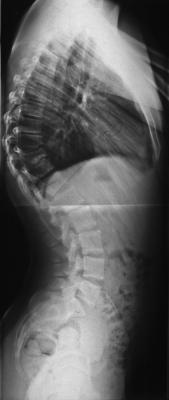

postoperative Bilder

Nur der vollständigkeit halber wollte ich noch die wirklichen postoperativen Bilder des Pat. aus dem Fernsehbeitrag zeigen. Dort wurden Bilder von einem anderen Pat. gezeigt, der präoperativ 95° hatte und viel Älter war.

Natürlich ist das optische für den Patienten wichtig, aber was für mich wichtiger ist, ist, wie sich die LWS postoperativ einstellt, ohne dass sie versteift werden muß. Wir konnten hier auf eine Lösungsop. von vorne verzichten und haben stattdessen von hinten viele kleine Osteotomien gemacht. Bei 75° präop sind 26° postop und eine gut balancierte LWS sehr erfreulich.

Man sollte diese Möglichkeit als Patient zumindest kennen, bevor man sich für oder gegen eine OP entscheidet.

- Man beachte die kurzbogige Kyphose mit den Keilwirbeln thrakolumbal und die kompensatorische Hyperlordose.

Der Pat. hatte hier häufig Schmerzen. - Kyphose_präop.jpg (8.7 KiB) 22717 mal betrachtet

- Durch die Ausgradung der BWS stellt sich die LWS automatisch physiologischer ein.

- Kyphose_postop.jpg (8.95 KiB) 22717 mal betrachtet